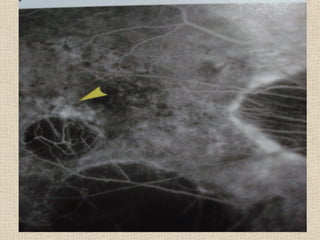

- retinal arterioles - exudate

retinal haemorrhage edema

microaneurysm

attached retina - vitreous opacity

hole /break vitreous bleed

- Retinal venules - pigmentation

detached retina detached choroid

outine of break

- ora serrata

/drusen